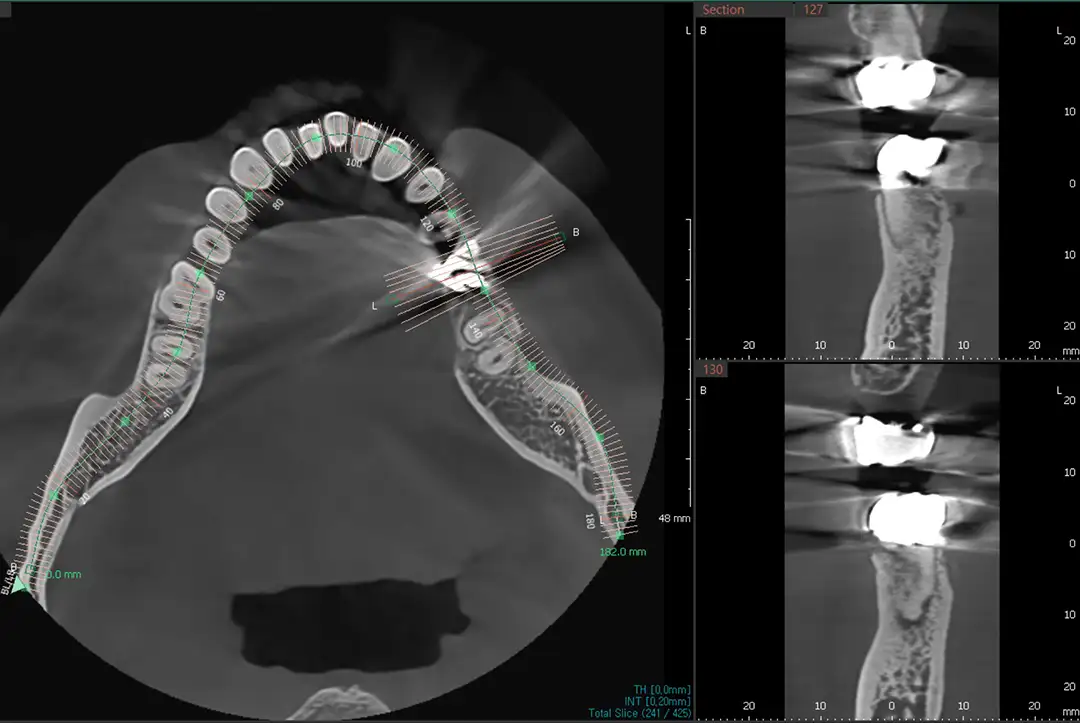

3D 디지털 진단을 통해 컴퓨터상에서 모의 수술을 먼저 시행한 후, 3D 프린터로 제작된 맞춤형 가이드를 이용해 최적의 위치에 정확히 식립하는 네비게이션 임플란트. 네비게이션 임플란트가 가능한 경우 추가금 없습니다.

트리오스5로 구강 스캔후 3D 프린터로 네비게이션 가이드를 출력합니다

CT 진단

파노라마 엑스레이 촬영시 3D CT 추가 비용 없습니다. 임플란트 진단 비용을 추가로 받지 않습니다.

임플란트 단계마다 필요시 CT를 촬영합니다. 확신보다 중요한 것은 확인입니다.